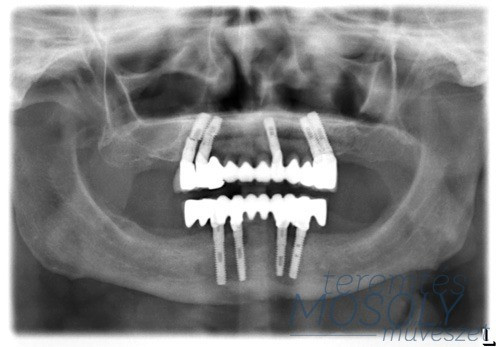

Sokan azonban nem tudnak vállalkozni ezekre a műtétekre, mivel költségesek, vagy épp nem megfelelő állapotban van a szájüregük. Az ő számukra megoldást jelent a Halász Klinika ALL-on-4 szolgáltatása, melynek során implantátumok és hidak segítségével pótolják az elvesztett fogakat.